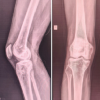

Each patient will undergo a thorough clinical examination, including history-taking and physical evaluation. Mechanical symptoms indicate that instability, restricted range of motion, and locking will be assessed. Special tests, like McMurray’s test and the hyperextension test, will be used to confirm clinical suspicion of a DM. MRI will serve as the gold standard for diagnosing the DM, classifying tear types, and identifying any associated intra-articular injuries. MRI will also be used during follow-up to assess meniscal healing and joint preservation. In addition, plain X-rays will be used preoperatively to assess joint alignment and exclude bony abnormalities such as osteophytes.

The patients were assessed at the 2 and 6 weeks, 3, 6, 13, and 24 months of surgery. Radiological and functional assessments were carried out at each visit. The MRIs were performed at the age of 6, 12, and 24 months to assess the integrity of cartilages, preservation of the joint, as well as meniscal repair. In addition, at ages 12 and 24 months, X-rays were performed to verify any degenerative changes at an early stage, such as the formation of osteophytes or a reduction in the space between the joint. X-rays will also be taken to evaluate any degenerative changes or joint space narrowing.